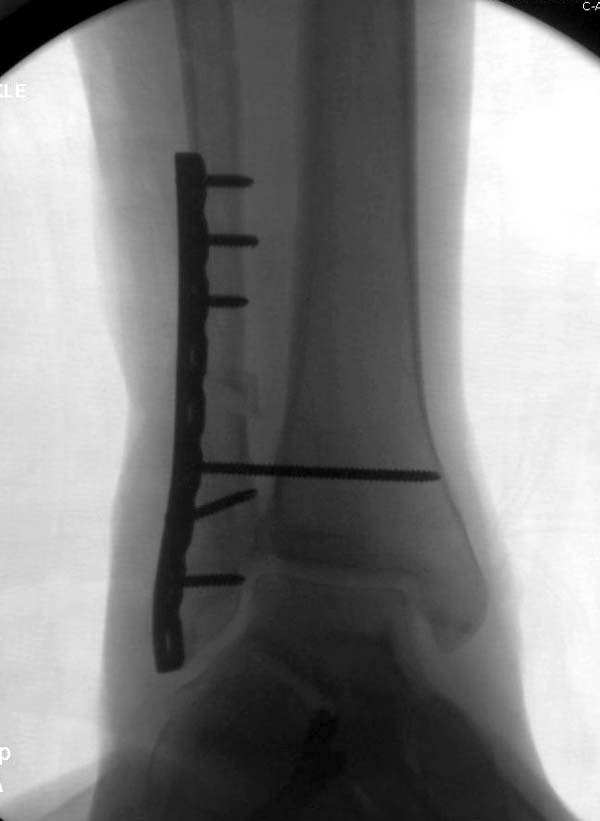

Здесь представлено решение похожей проблемы. Больной в течение года лечился консервативными мерами, и боли в голеностопе были основным показанием к операции.

Проведена обычная стандартная процедура по исправлению неудовлетворительного состояния голеностопного сустава, где кроме удлинения малоберцовой с применением compression tension device за проксимальный конец пластины, проведено замещение трикортикальным графтом из крыла, освобождение синдесмоза и медиальной щели от

фибротических масс с фиксацией.

Не могу дать ссылку на сравнительную литературу

"артродез против восстановления", но можешь поверить мне, что несмотря на продолжительный период до восстановления сустава, после таких операции больные чувствует намного легче чем после расхваливаемого артродеза.